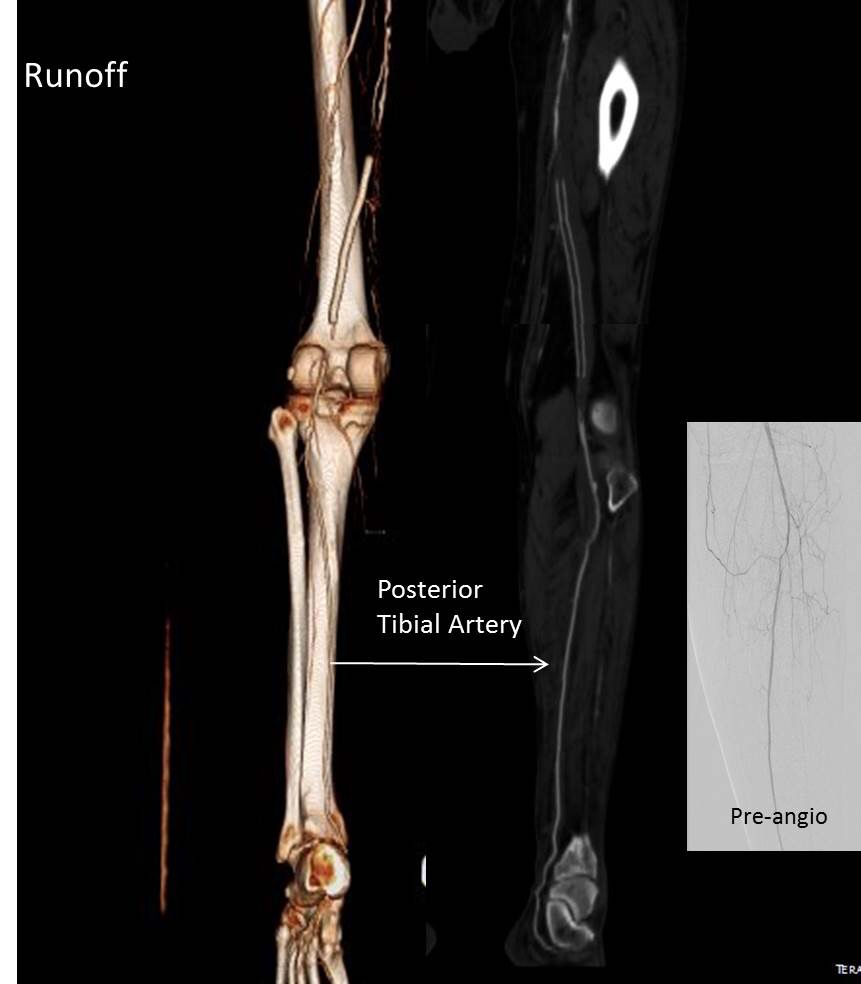

Let me show you one of the first cases I did after returning to Cleveland. I am now practicing at Fairview and Avon Hospitals, premier flagship hospitals in the Cleveland Clinic fleet, on Cleveland’s west side, and a patient arrived while I was on call with sudden onset of pain in his leg from a lack of blood flow. He had occlusive atherosclerotic plaque extending from his external iliac artery to the above knee popliteal artery causing ischemic rest pain.

I contacted LeMaitre Vascular and got in touch with your representative, L. Fisher, who promptly sent the Moll Ring Cutters I needed to perform a remote endarterectomy of the patient’s occlusive external iliac and superficial femoral artery plaque. The technical details of remote endarterectomy are have been covered in my blog (https://vascsurg.me/?s=endore), but in the end, through a 7cm incision in the groin (don’t believe the hype, this is minimally invasive), I restored his arteries to their original open condition. Shown below are the results. It was with great sadness that I heard that the LeMaitre Vascular equipment being sent were the last of the stock available in North America. The patient did very well, with the operation completed well before lunch, and is recovering rapidly from his small wound and big rescue. He gets to walk out of the hospital on two legs, but also with the surety that he avoided a major bypass operation, and avoided the short term gains of stenting from the aorta to the profunda -more peel packs and landfill items and a dubious long term durability. Hey, I even used a XenoSure patch on the common femoral.